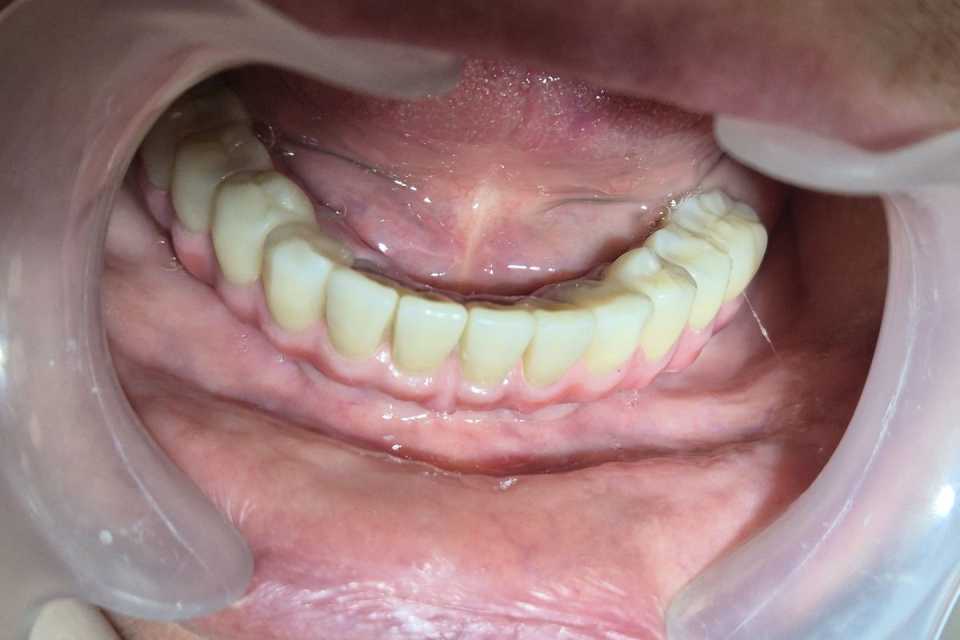

Pacienta, în vârstă de 77 de ani, purtătoare veche de proteză mobilă la nivel mandibular, a dezvoltat o resorbție osoasă severă, ceea ce a dus la dificultăți majore în masticație și imposibilitatea purtării protezei. Se prezintă cu dorința de a beneficia de o lucrare fixă la nivelul mandibulei.

Cu ajutorul a 4 implanturi dentare Mega-Gen AnyRidge, inserate interforaminal (tehnica All-on-4), realizăm o lucrare din ceramică pe suport de titan, formată din 12 elemente, înșurubabilă pe suport multiunit.